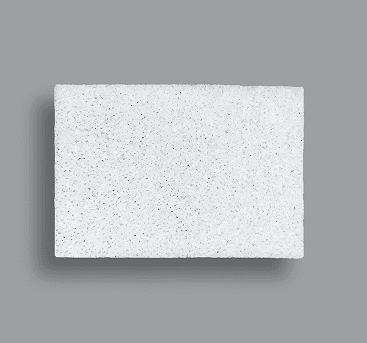

Sheet